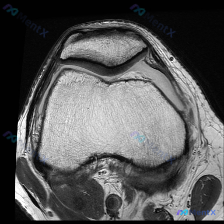

今天看到一个很有代表性的读片问题,整理出来和大家分享讨论:问题是判断这张髌股关节轴位T1加权MRI上有没有软骨异常,我们一步步梳理思路。 一、先看影像基本信息 这是一张膝关节MRI的轴位T1加权图像,扫描层面位于膝关节上方的髌股关节层面: 1. 骨骼结构:髌骨位于前方,骨皮质边缘清晰,骨髓脂肪信号正...

刚整理了一份膝关节MRI的读片分析,核心问题是软骨异常,分享一下完整的分析思路给大家。 病例影像基本信息 这是一张膝关节髌股关节层面的轴位MRI图像,从信号特点判断是质子密度加权脂肪抑制序列(PD-FS)或T2脂肪抑制序列,清晰度尚可,无明显运动伪影,这种序列对关节积液、软骨损伤非常敏感。 影像学核...